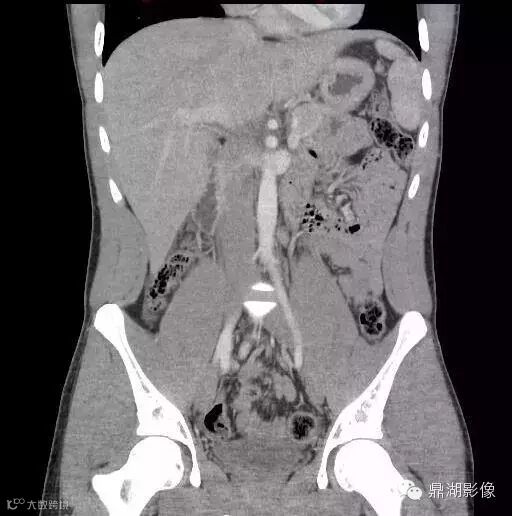

22岁男性,发热,大便潜血试验阳性,脐部下方见管状结构并环形强化(箭),周围可见炎性改变,邻近小肠壁增厚。